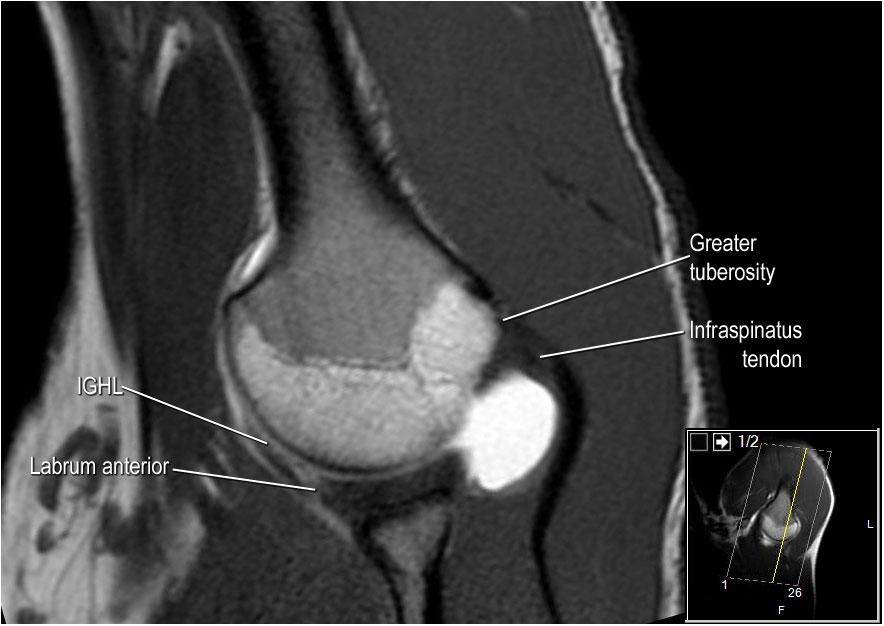

Hình ảnh mặt sau

Hình ảnh thể hiện các cơ và gân của cơ trên gai, cơ dưới gai và cơ tròn bé. Tất cả đều bám vào mấu động lớn.

Các cơ và gân chóp xoay có chức năng ổn định khớp vai trong quá trình vận động.

Nếu không có chóp xoay, chỏm xương cánh tay sẽ trượt lên một phần ra khỏi hõm ổ chảo, làm giảm hiệu quả hoạt động của cơ delta.

Rách lớn chóp xoay có thể khiến chỏm xương cánh tay di chuyển lên trên, dẫn đến hình ảnh chỏm xương cánh tay nằm cao bất thường.